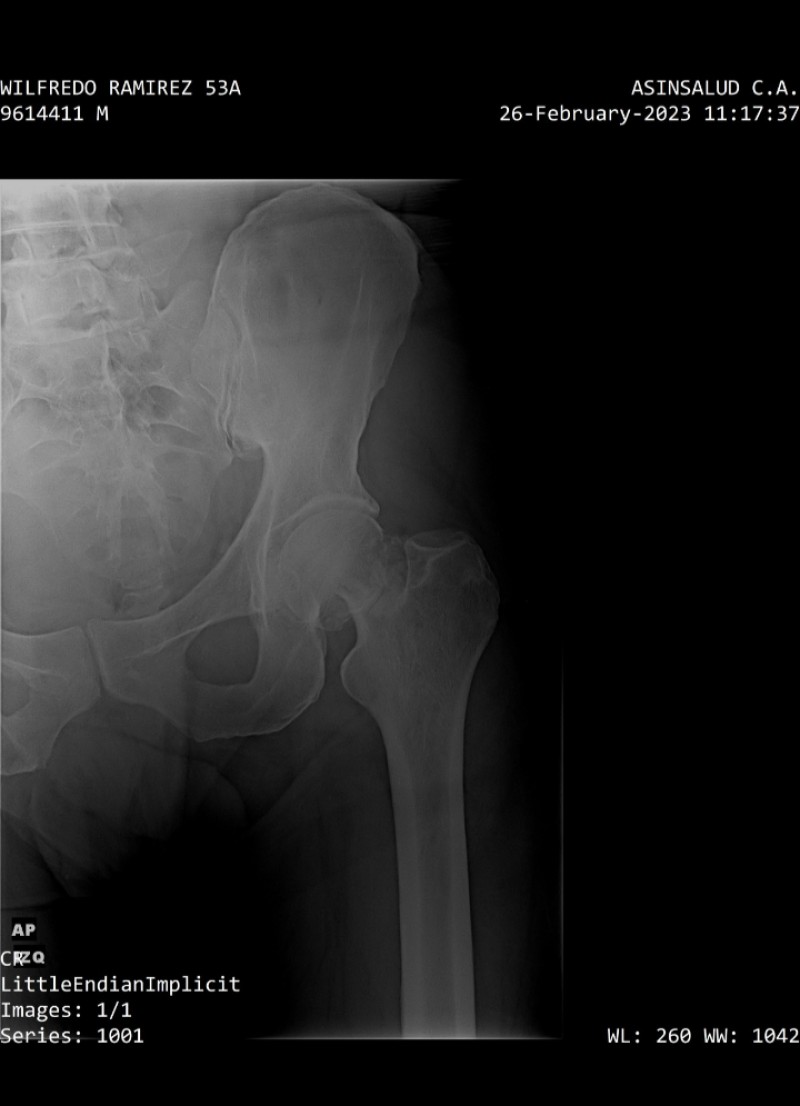

Buenos Días, presento fractura de cadera izquierda, al sufrir caída . Amerita Opercion Urgente y colocación de prótesis total de cadera doble movilidad, necesito de su apoyo para asi volver a caminar.